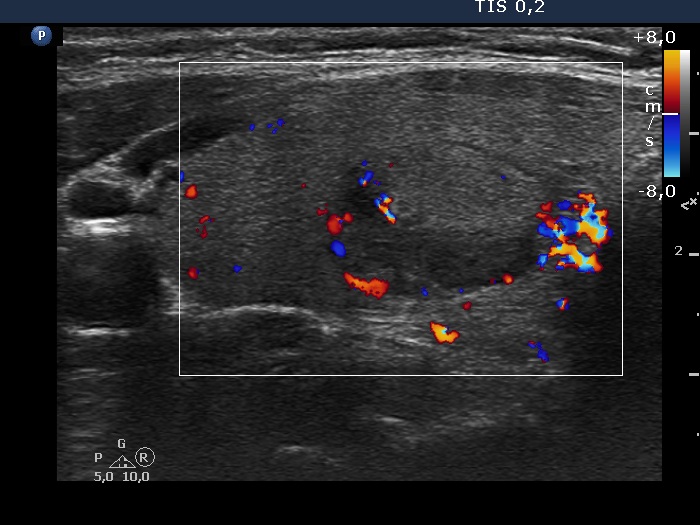

Comment. The judgement of several ultrasound characteristics is not easy in this case. First, the echogenicity of the nodule: echonormal and hypoechoic parts occur in roughly equally. The borders present undulation at the ventral and lower parts which can be regarded pathological. Finally, the intranodular echogenic figures are also difficult to judge.